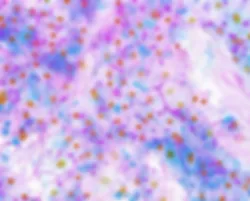

Steatosis

Lipid Droplet Accumulation

Hoechst (Nuclei) LipTOX (Neutral Lipids)

ER Stress

BIP/GRP78 Expression

Hoechst (Nuclei) BIP/GRP78 (ER Stress)

Cholestasis

Bile Canaliculi Loss

Hoechst (Nuclei) Phalloidin (Actin)

Lysosomal Disruption

Lipofuscin Buildup

Hoechst (Nuclei) Lysosomal (Autofluorescence)

Mitochondria

Fission and Fusion

Hoechst (Nuclei) Mitotracker

Cytotoxicity

Nuclei Loss and Morphology

Hoechst (Nuclei)